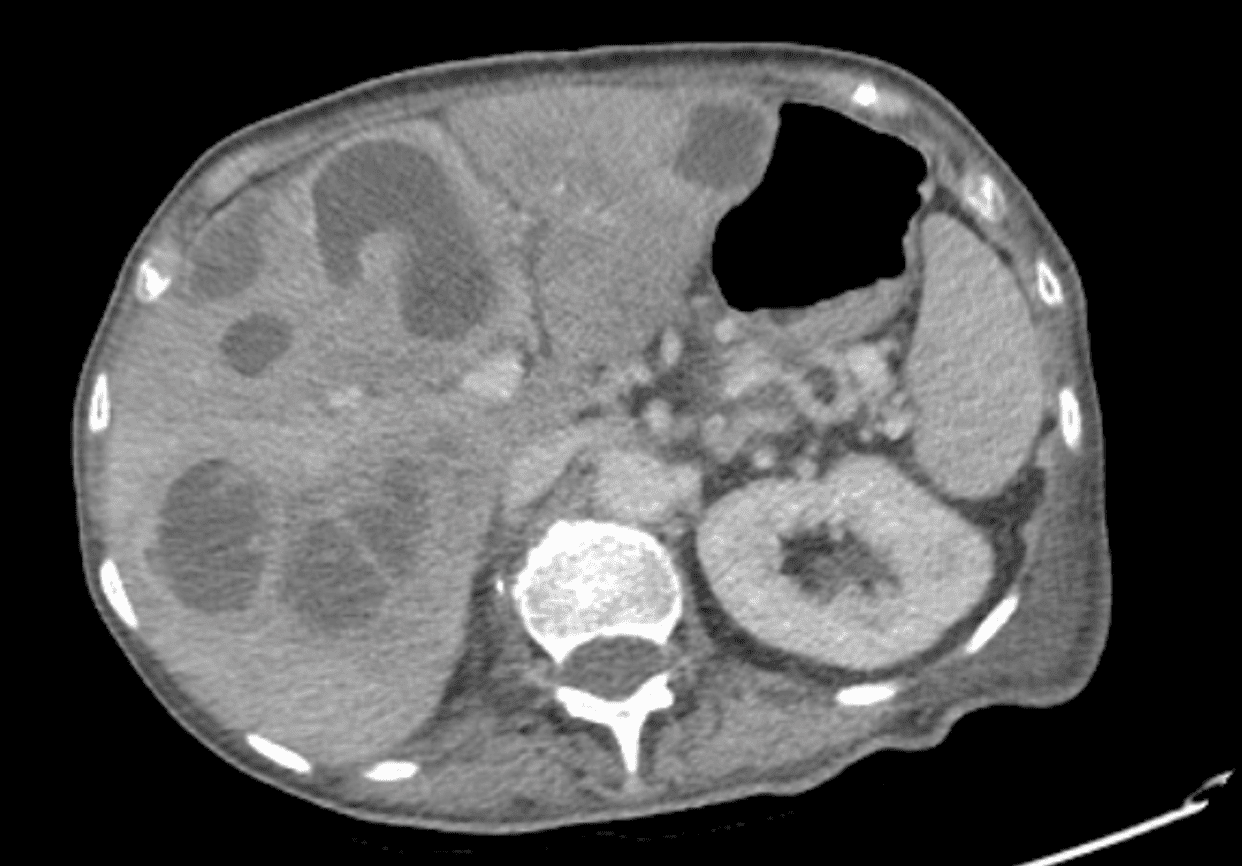

Se realiza una ecografía abdominal a pie de cama con hallazgo de múltiples imágenes hipodensas con contenido heterogéneo y áreas quísticas en hígado, sugestivas de metástasis, por lo que se solicita TAC abdominopélvico que confirma dichas lesiones con componente necrótico sobreinfectado y una con extensa neoplasia rectal localmente avanzada.